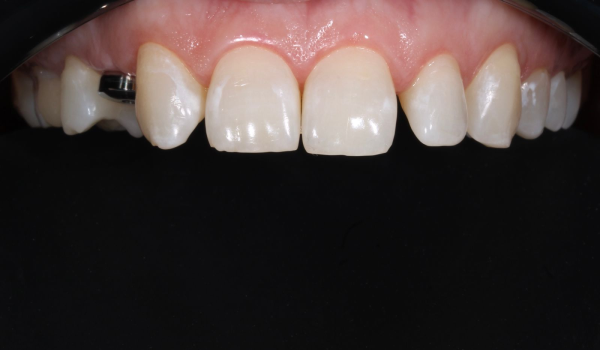

Истории лечения наших пациентов в формате "до-после"

4. Примерки и фиксация

примеряем виниры и корректируем по вашим пожеланиям